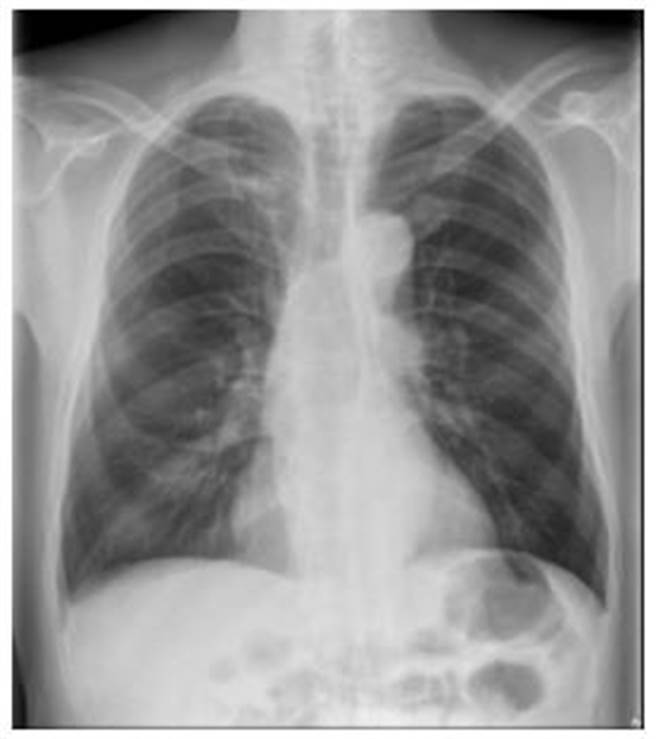

一位62岁的上班族男子,连续四年做胸部X光检查,都未发现异常,因他长年抽菸,近月採低剂量肺部电脑断层检查,没想到竟然在右上肺叶找到一颗1.5公分的肿瘤,确诊罹患肺癌。澄清医院柏忕健康管理中心医学影像科洪盈盈医师表示,胸部X光敏感度有所限制,有时候1.5公分的肿瘤也不一定看得到。

洪盈盈表示,一般民眾的迷思认为「定期胸部X光检查,就可以发现早期肺癌」,事实上,「1公分以下的肺部肿瘤很难发现」。有时候,1.5公分的肿瘤也不一定看得到,此个案就是很典型的例子。因为很多肺癌早期生长时密度很低,呈现出来的毛玻璃影像看起来淡淡的,也有可能藏在胸椎、心臟、肋骨、横膈膜或肝臟前后方,这些皆是X光影像的死角。